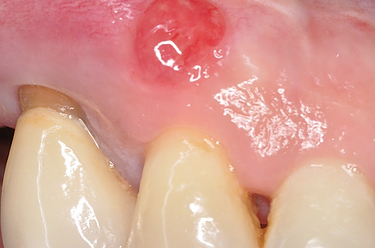

Absceso Periapical Crónico

Un absceso periapical crónico es una infección prolongada en la punta de la raíz del diente que forma una bolsa de pus.

Los pacientes pueden tener dolor leve o no tener síntomas, pero notar una fístula en la encía.

El tratamiento incluye un tratamiento de conducto y, en algunos casos, una cirugía apical. Es crucial tratarlo para evitar la propagación de la infección.